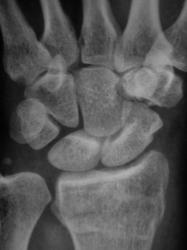

Пол пациента: Мужской пол Тип патологии: Травма Область исследования: Скелетно-мышечная система Методы исследования: Rg Травма. Пациент направлен врачом хирургом на рентгенографию лучезапястного сустава. Произведено исследование. Ваше мнение коллеги? Thu, 15/10/2009 - 21:47 #1 Наталия Offline Last seen: 8 years 8 months ago Joined: 30.07.2008 - 13:24 Posts: 538 Откол части шиловидного отростка локтевой кости, перелом лучевой кости в питичном месте, перелом ладьевидной кости. Может отрыв крючка. Thu, 15/10/2009 - 22:25 #2 v1tal Offline Last seen: 4 years 10 months ago Joined: 07.06.2008 - 19:41 Posts: 1779 Можно добавить краевой перелом кости-трапеции. "Знаешь, у некоторых врачей есть комплекс мессии — им необходимо спасать мир. А у тебя комплекс Рубика — тебе необходимо решать головоломки." Sun, 18/10/2009 - 23:33 #3 Катенёв Валенти... Offline Last seen: 7 years 1 month ago Joined: 22.03.2008 - 22:15 Posts: 54876 Так выходит - 3 перелома!? Mon, 19/10/2009 - 20:15 #4 Анатолий Владим... Offline Last seen: 7 years 11 months ago Joined: 16.10.2009 - 21:16 Posts: 1941 В ладьевидной кости в норме часто можно наблюдать ступеньку по наружному контуру, которая симулирует перелом. Для окончательного решения вопроса необходима рентгенограмма костей запястья в косой проекции.

Откол части шиловидного отростка локтевой кости, перелом лучевой кости в питичном месте, перелом ладьевидной кости. Может отрыв крючка.

Можно добавить краевой перелом кости-трапеции.

Так выходит - 3 перелома!?

В ладьевидной кости в норме часто можно наблюдать ступеньку по наружному контуру, которая симулирует перелом. Для окончательного решения вопроса необходима рентгенограмма костей запястья в косой проекции.